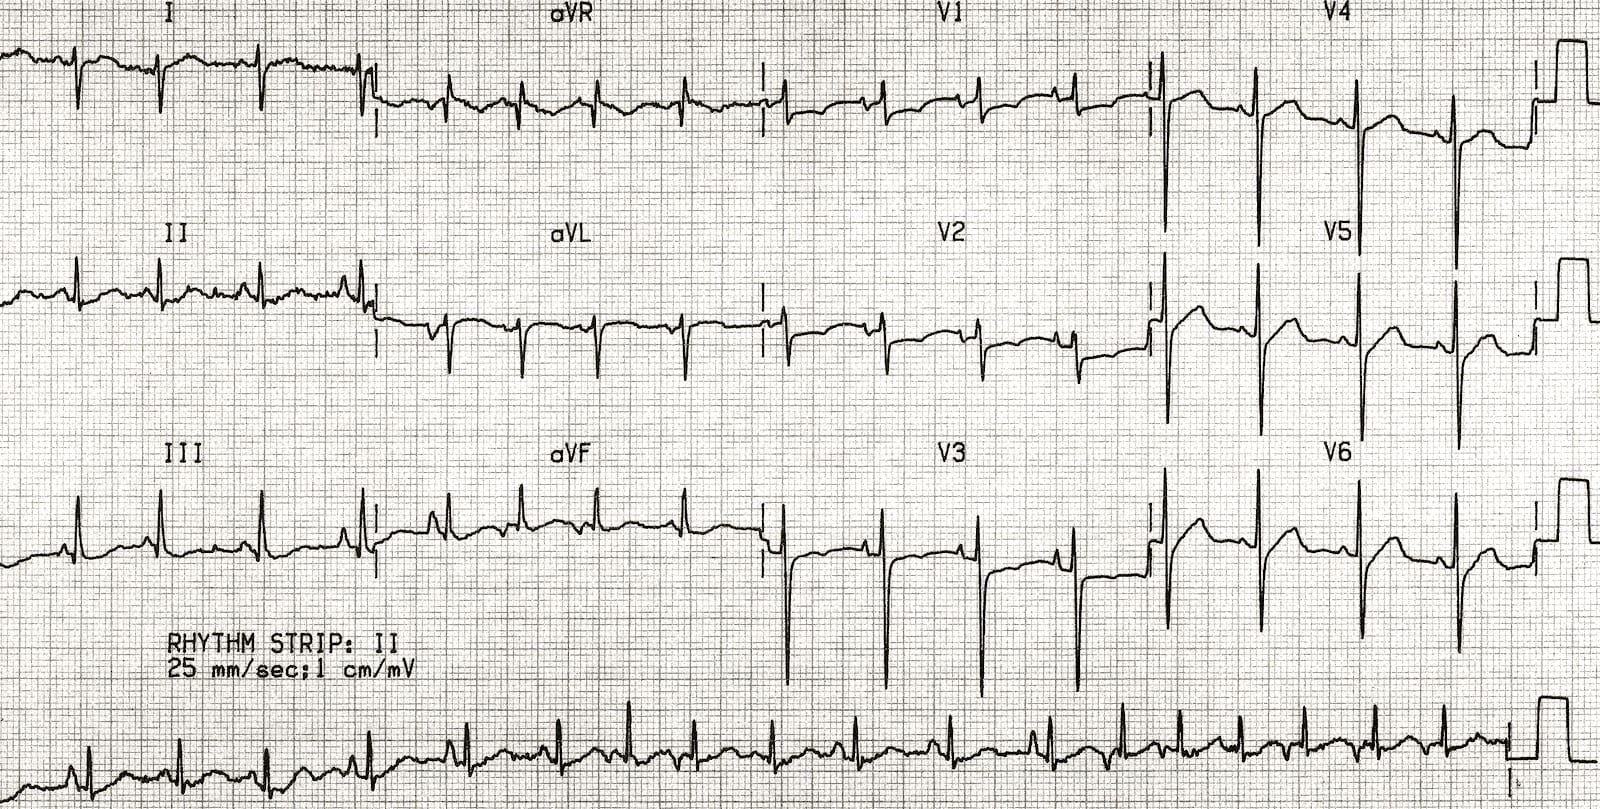

ST elevation can be clearly seen in V2-V4 and V5, V6, I, and aVL. This corresponds to the myocardial territory of the anterior and lateral wall.